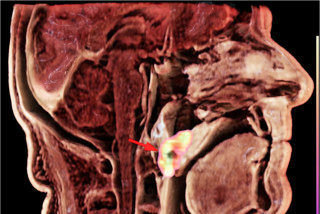

A CAD representation (a) and 3D printed model (b, c) of the pathologically altered mandible were created for preoperative planning and osteosynthetic plate prebending. Personalized surgical guides designed for mandible reconstruction surgery with free fibula flap are shown (d, e). The fitting of the flap's bone fragment to the native mandible post plate fixation is depicted (f). A cinematic-rendering reconstruction from a follow-up CT scan, taken 13 months after the reconstruction surgery, demonstrates complete healing of the bone fragment; its edges are marked with red arrows (g). All figures courtesy of Dr. Vjekoslav Kopačin, PhD, Department of Diagnostic and Interventional Radiology, University Hospital Center Osijek, Croatia, and presented at ECR 2024.

Cinematic rendering transforms standard CT and MRI data into photorealistic 3D images by precisely simulating light propagation and interaction, and it enhances depth perception in 3D reconstructions, which is crucial for through-plane views, she explained. It allows surgeons to visualize anatomical details from various perspectives, closely resembling what they encounter in the operating room.

"The increased realism may help mitigate the impact of unexpected findings and anatomical variations during surgery," stated Ivančić and coauthor Dr. Vjekoslav Kopačin, PhD, who shared their experiences at ECR 2024. "It provides a lifelike portrayal of anatomical features, offering improved depth and structure delineation. In instances where 3D printing is unavailable, it can serve as a viable alternative.